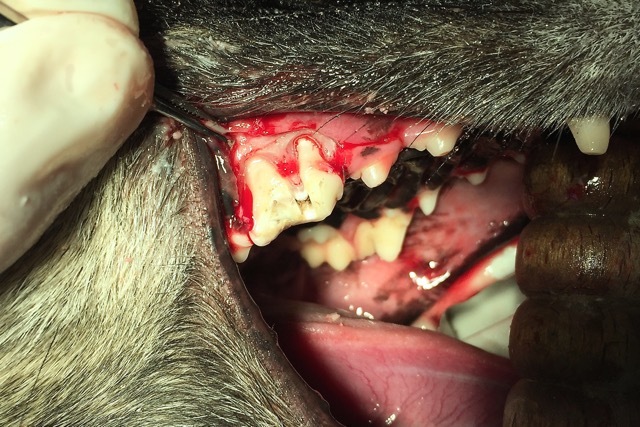

Seit einigen Tagen war sie darüber hinaus auch ruhiger geworden und zog sich immer mehr zurück. Die Untersuchung der Maulhöhle und der Zähne brachte schnell ans Tageslicht, was die Ursache dafür war. „Lotte“ hatte Zahnschmerzen, und das wohl schon seit einiger Zeit. Der Reißzahn im rechten Oberkiefer war schon vor längerem abgebrochen, was man an der dunklen Verfärbung an der Bruchstelle erkennen konnte (Foto 1). Auch ein unangenehmer, modriger Geruch machte sich beim Öffnen des Fanges im Behandlungsraum breit. Der Zahn war abgestorben und durch den offenen Wurzelkanal waren Bakterien in die Tiefe gelangt, die eine schmerzhafte Entzündung des Kiefers verursacht hatten. Schnell musste der Hündin geholfen werden.

Bei „Lotte“ lag jedoch eine komplizierte Fraktur mit gespaltener Krone vor, so dass tatsächlich nur eine Extraktion des Zahnes in Frage kam. Solch ein dreiwurzeliger Zahn kann nicht im Ganzen gezogen werden. Die Wurzeln sitzen fest im Kiefer und sind gerade bei schon älteren infizierten Zähnen sehr spröde und morsch und brechen leicht in der Tiefe ab. Daher ist eine kieferchirurgische, offene Extraktion die Methode der Wahl. So wurde bei „Lotte“ die Mundschleimhaut um den Zahn herum gelöst und der Kieferknochen freigelegt. Dann wurde der Knochen mit einem wassergekühlten Bohrer über den Zahnwurzeln entfernt, bis diese komplett sichtbar waren. Anschließend wurde der Zahn mit einem Fräser in drei Teile geteilt und die einzelnen Wurzeln mit verschiedenen Hebeln gelockert, um sie danach separat ziehen zu können (Foto 2). Besonders wichtig ist es, dass keine Wurzelreste im Kiefer verbleiben, denn diese verursachen weiterhin Schmerzen und führen zu einer Abszessbildung im Kieferknochen. Nach Glättung der scharfen Knochenkanten wurde die Schleimhaut wieder über die Wunde gelegt und mit einer Wundnaht mit Einzelheften eines resorbierbaren Nahtmaterials verschlossen, welches sich nach einigen Wochen von selbst auflöst (Foto 3).